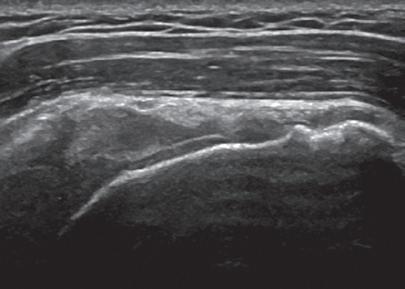

SONOGRAPHIC APPEARANCES OF NORMAL STRUCTURES

Musculoskeletal structures have characteristic appearances on ultrasound imaging.2 Normal tendons appear hyperechoic with a fiber-like or fibrillar echotexture (see Fig. 1.4).3 At close inspection, the linear fibrillar echoes within a tendon represent the endotendineum septa, which contain connective tissue, elastic fibers, nerve endings, blood, and lymph vessels.3 Continuous tendon fibers are best appreciated when they are imaged long axis to the tendon. On such a long axis image, by convention the proximal aspect is on the left side of the image, with the distal aspect on the right. In short axis, normal hyperechoic tendon fibers appear as bristles of a brush seen on end (see Fig. 1.9A). Normal muscle tissue appears relatively hypoechoic (Fig. 1.6). At closer inspection, the hypoechoic muscle tissue is separated by fine hyperechoic fibroadipose septa or perimysium, which surrounds the hypoechoic muscle bundles. The surface of bone or calcification is typically very hyperechoic, with posterior acoustic shadowing and possibly posterior reverberation if the surface of the bone is smooth and flat (Fig. 1.6). The hyaline cartilage covering the articular surface of bone is hypoechoic and uniform (Fig. 1.7A and B), whereas the fibrocartilage, such as the